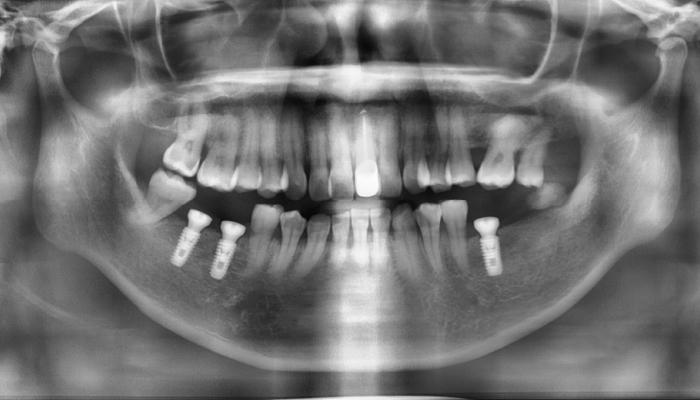

상악동거상술 수술사진

상악동거상술 전후 사례

• 식립 전

식립 후

• 식립전

식립후